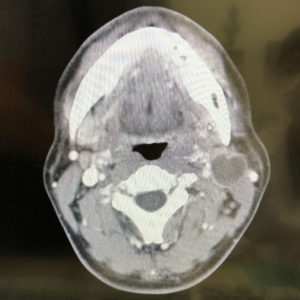

午前に問診と触診、採血。午後に組織を取って調べた。組織を取った時には、「膿疱ではないか」という言葉も聞かれた。人は都合のいい言葉の方を信じたがるものだ。俺もそっちの可能性が大きいだろうな、位に考えた。2日後(つまり今日)には造影剤を使ったCTスキャンの予約があり、むしろそれはおまけくらいになるのではないかと。

しかし、「残念ながら」だった。腫瘍があって、悪性なのだと。リンパ節の腫れそのものは腫瘍ではなく、元になる腫瘍が付近にあって、それに反応した結果だろうという。なので、リンパ節腫瘍とは診断されなかった。

一人で検査結果を聞きにきている俺にショックを与えないためだろうか、腫瘍や癌という言葉さえ使わず、婉曲的な言い回しをするので、こちらが「腫瘍の治療となると」とか「悪性ということですね?」とはっきり言って確かめ、治療をどこでするかという話になって、国立がん研究センター中央病院への紹介を受けた。